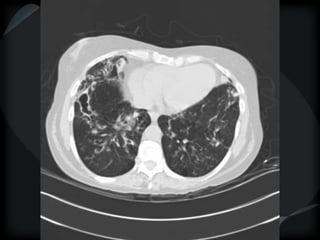

RETICULAR PATTERN - UIP

 peripheral reticular lines / inter and intralobular septae

 honeycomb

 Traction bronchiectasis

 None or minimal ground glass

 Gradient increasing from apex to base

 Skip areas

 Diagnostic accuracy high